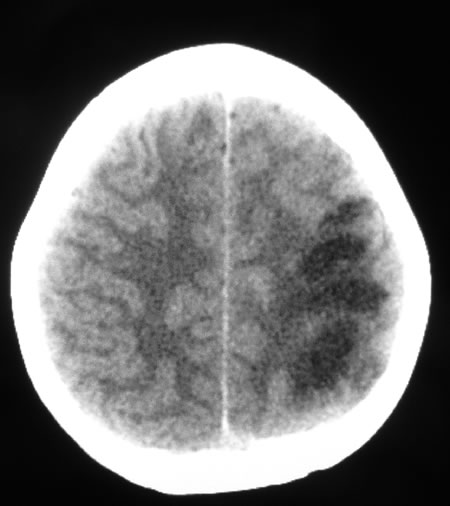

La biopsia duodenale mostra una mucosa di tipo

3B con villi corti a base ampia e rarefatti come da patologia

malassorbitiva; presenti i microvilli; evidenza di fitto

infiltrato linfoplasmacellulare e localmente eosinofilo del

corion con ectasie linfatiche polifocali (fig.

3)

La laparoscopia esplorativa eseguita dopo assunzione orale di un pasto grasso (latte di soja) tinto con un colorante alimentare ha evidenziato diffusa trasudazione del chilo attraverso la parete intestinale. Sono risultate infine dirimenti le sezioni istologiche che hanno messo in luce l'ectasia dei vasi linfatici. (fig. 4)